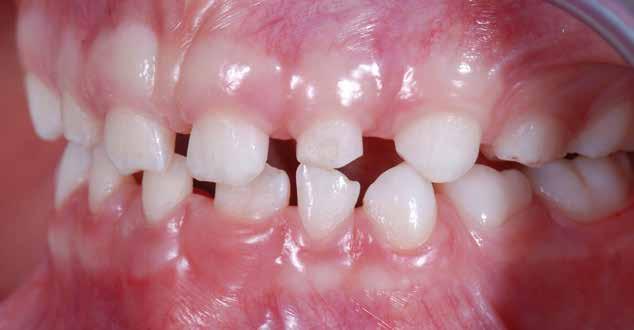

Presentazione del caso > F.V, bambino di cinque anni, presenta una malocclusione di II Classe scheletrica, III Classe dentale molare e canina destra e sinistra, morso inverso anteriore. Le arcate dentali mostrano usura degli elementi dentari anteriori a causa dell’occlusione patologica. Le linee mediane, superiore ed inferiore, sono centrate; il frenulo labiale superiore patologico per un’eccessiva estensione inter-incisale.

Il piano di trattamento prevede l’utilizzo di un dispositivo elastodontico di III Classe, da portare per due ore diurne e tutte le notti in modo passivo, senza effettuare alcun esercizio, al fine di ripristinare una relazione molare e canina bilaterale di I Classe ed il corretto avanzamento maxillare e inibire l’eccessiva crescita mandibolare. È possibile ottenere il risultato in pochissimi mesi di terapia, essendo la crescita del paziente molto attiva.

Dall’esame clinico si evince la III Classe dentale, l’inversione anteriore e l’over-jet negativo.

Una volta ottenuta la correzione del rapporto molare ed incisale, l’apparecchio elastodontico verrà portato dal paziente solo durante la notte per stabilizzare il risultato ottenuto e guidare l’eruzione degli elementi dentari per un totale di quattordici mesi di terapia. ad inizio trattamento :

Considerazioni > L’analisi cefalometrica ad inizio trattamento dimostra la II Classe scheletrica con protrusione del mascellare superiore e prognazia mandibolare; tendenza alla crescita verticale. L’esame clinico evidenzia una protrusione mandibolare funzionale.